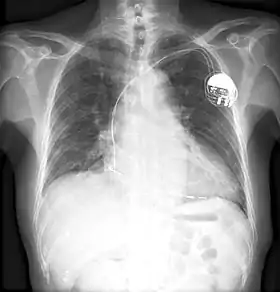

Otis Boykin naît en 1920 à Dallas au Texas. Sa mère est une femme de chambre, décédée d'une insuffisance cardiaque quand Otis a un an. Cela l'inspire à créer le stimulateur cardiaque[2]. Son père, Walter, est menuisier puis plus tard ministre.

Boykin a breveté 28 appareils électroniques. L'une de ses premières inventions est une résistance à fil améliorée, qui réduit l'inductance et la réactance, en raison de l'arrangement physique du fil[7]. D'autres inventions notables comprennent une résistance variable utilisée dans les missiles guidés[8]. Son invention la plus célèbre est probablement une unité de contrôle pour le stimulateur cardiaque artificiel[2]. L'appareil utilise essentiellement des impulsions électriques pour maintenir un rythme cardiaque régulier.